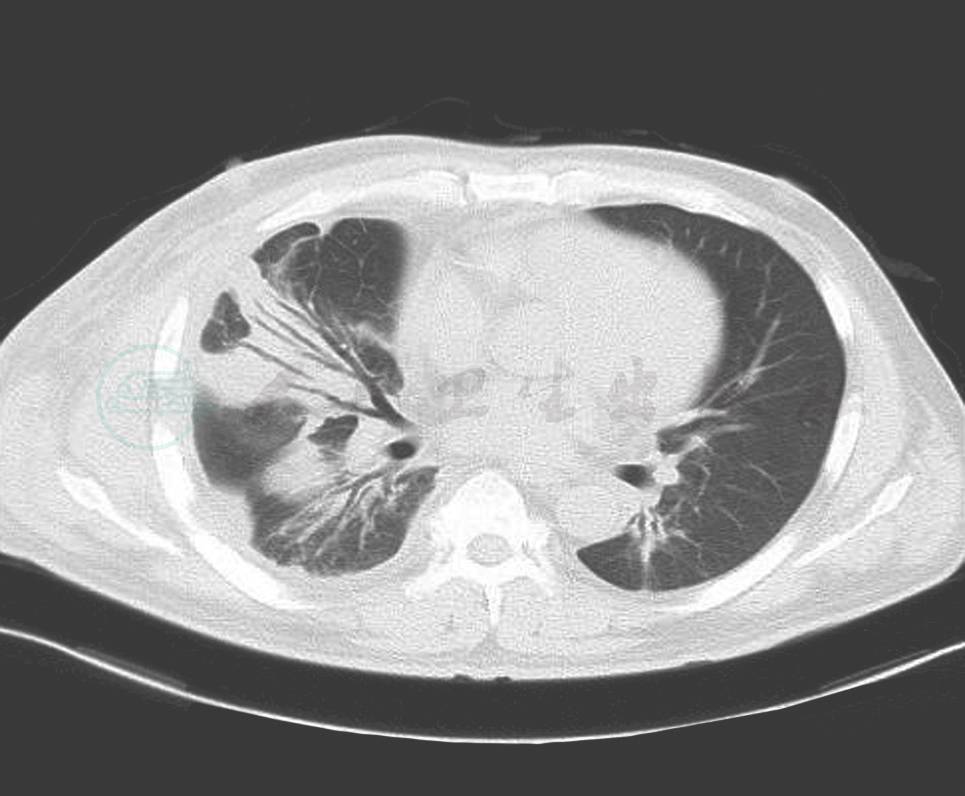

血象、血沉、结核三项、G试验、呼吸道病原及风湿免疫检查均未见异常。T-SPOT阳性。IgG 1410mg/dl,IgG4 355mg/dl。胸腔积液:送检胸水涂片及细胞病理学未见阳性结果;常规生化结果考虑为渗出液。胸部CT:右侧胸壁软组织占位并肋骨破坏及纵隔、腋窝淋巴结多发转移,不除外胸壁来源的恶性肿瘤;双肺炎症(图2、图3、图4)。小器官超声:双侧腋下多发肿大淋巴结。我院病理会诊(外院腋窝淋巴结标本):其内见血管内皮细胞增生显著。我院右侧腋窝淋巴结活检病理:Castleman病(巨大淋巴结增生症),透明血管型。免疫组化染色结果:CD3(T 细胞 +),CD20(B 细胞 +),CD21(+),CD34(血管 +),CD38(+),Ki-67(+25%~50%)。我院病理会诊(外院胸壁皮肤标本):考虑血管源性肿瘤,以上皮样血管内皮细胞瘤可能性大。我院右胸腹部皮肤活检:不除外血管肉瘤。北京协和医院病理会诊:(外院淋巴结):淋巴结结构存在,淋巴滤泡生发中心缩小,滤泡间见较多浆细胞浸润伴小血管增生。(外院皮肤):真皮胶原纤维及小血管显著增生,伴少许淋巴细胞浆细胞浸润;结合免疫组化考虑为IgG4相关性疾病,建议结合临床并作相关检查及测定血清IgG4水平。(我院淋巴结):CD138(+)、CD38(+)、IgG4/IgG(大于 40%)、IgG4(100 个 /HPF)。(我院皮肤):CD138(+)、CD38(+)、IgG45、IgG4(100 个 /HPF)。诊断考虑:淋巴结:Castleman disease。皮肤:不除外高分化血管肉瘤。

图2 治疗前(肺部)